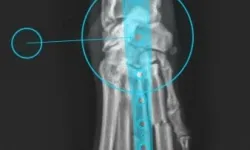

Pacient č. 3. - pooperační rtg, stav po osmi měsících.

Pacient č. 3. - pooperační rtg 2., stav po osmi měsících.

Pacient č. 3

• Plemeno sheltie, pohlaví fena, stáří 5 let

• Příčina kulhání –  úraz zápěstí z přetížení

• Diagnoza HEI – hyperextenzní poranění

• Terapie: PCA – pankarpální artrodéza